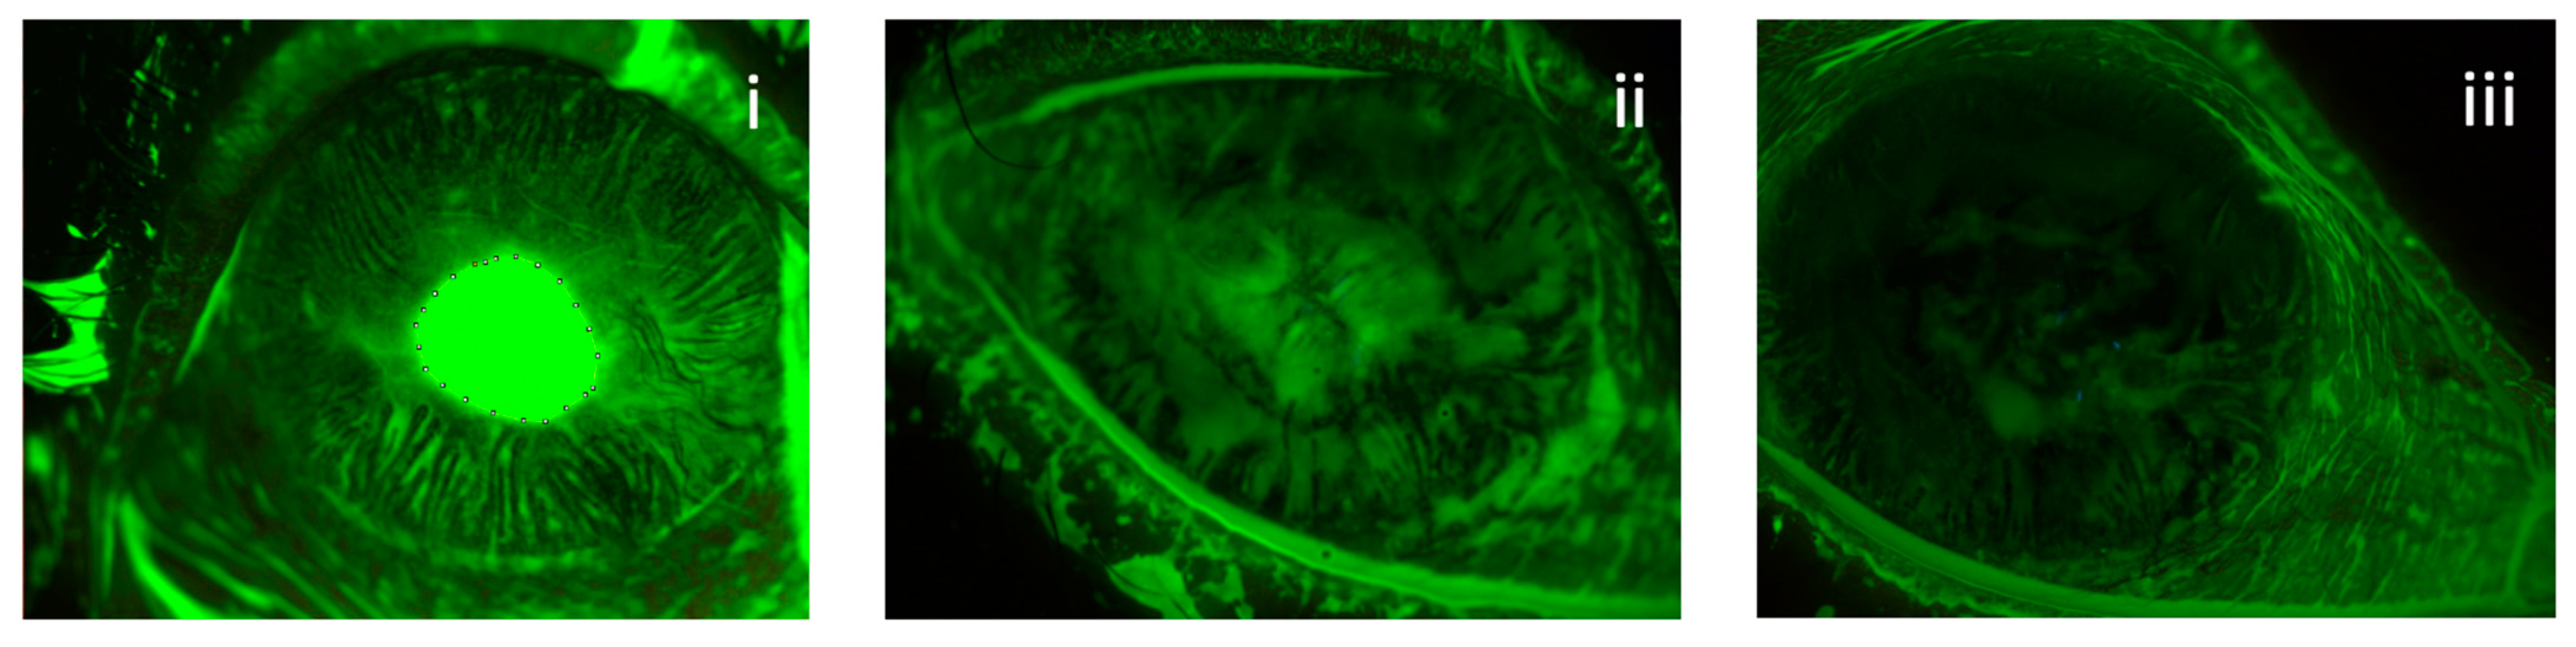

3.3. Corneal Nerves